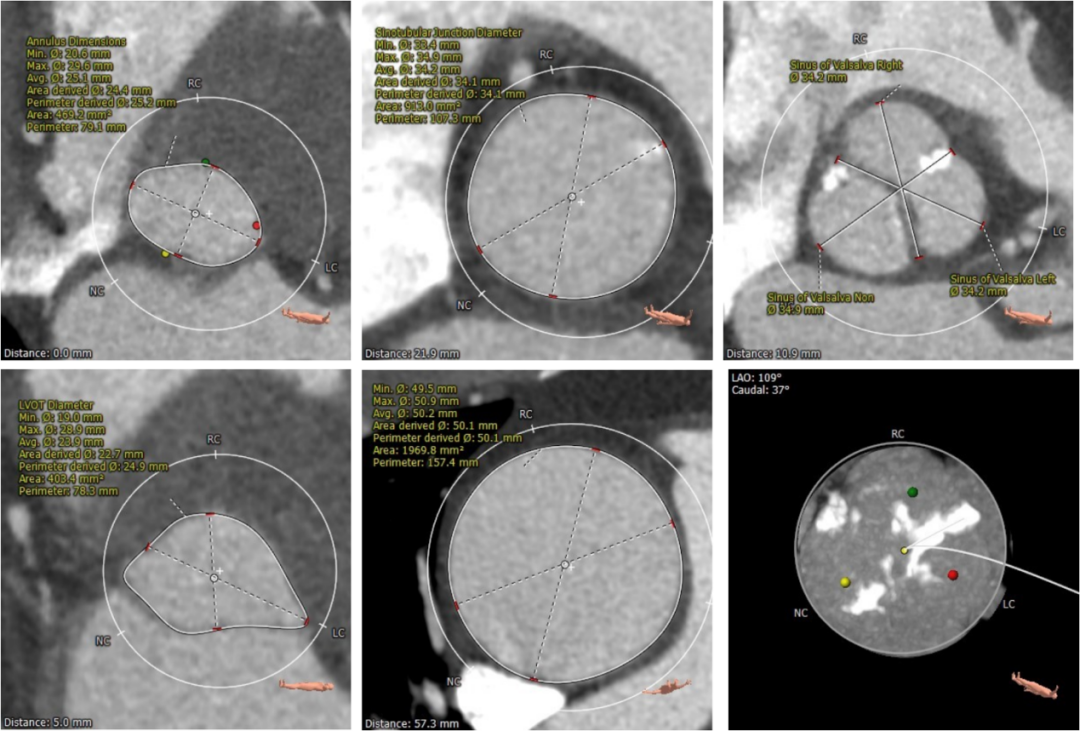

术前CT评估:

三叶式主动脉瓣,中度钙化并增厚,钙化分布不均匀,左右交界处存在似嵴样钙化。

左右冠高度尚可,左冠瓣瓣叶长度偏长,综合瓦氏窦内径等因素考虑,冠脉遮挡风险小。

左室流出道内径与瓣环内径相近,瓦氏窦,窦管交界内径可,升主动脉最宽处内径50mm,升主动脉瘤诊断明确。

左室腔内径可,心室壁增厚。

主动脉瓣环与水平面夹角可,非横位心,主动脉弓降部角度较锐利,弓部宽度尚可。

主动脉根部测量

瓣上结构测量

冠脉阻挡风险及钙化评估